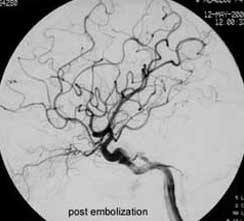

二、脑动静脉畸形(AVM)

---- Spetzler对AVM的分级方法已越来越多地被人们接纳和采用。脑AVM最危险的症状之一是出血。AVM每年的出血率为3%~4%,第一年内再出血约6%。每次出血的致残率为30%,病死率为12.5%,而积极治疗的总残废率加病死率在10%以下。

血管内栓塞对于单支或少数供血动脉的AVM,特别是新近出血的病例,可以达到微侵袭、痛苦小、疗效迅速的目的。

近来改变栓塞方式,将导管直接放置 畸形血管团内,注射NBCA胶,可使畸形团的解剖 治愈率提高至27%。再加上更细、超滑的微导管问世,栓塞的并发症更为降低。针对大型、功能区 的AVM栓 塞可缩小其体积,改善血液动力学分布,以利于显微外科技术切除或放射外科治疗,是后二者的重要辅助手段。